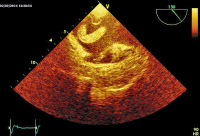

Abbildung 4: Thromboembolus im rechten Vorhof (modifizierter bikavaler Schnitt).